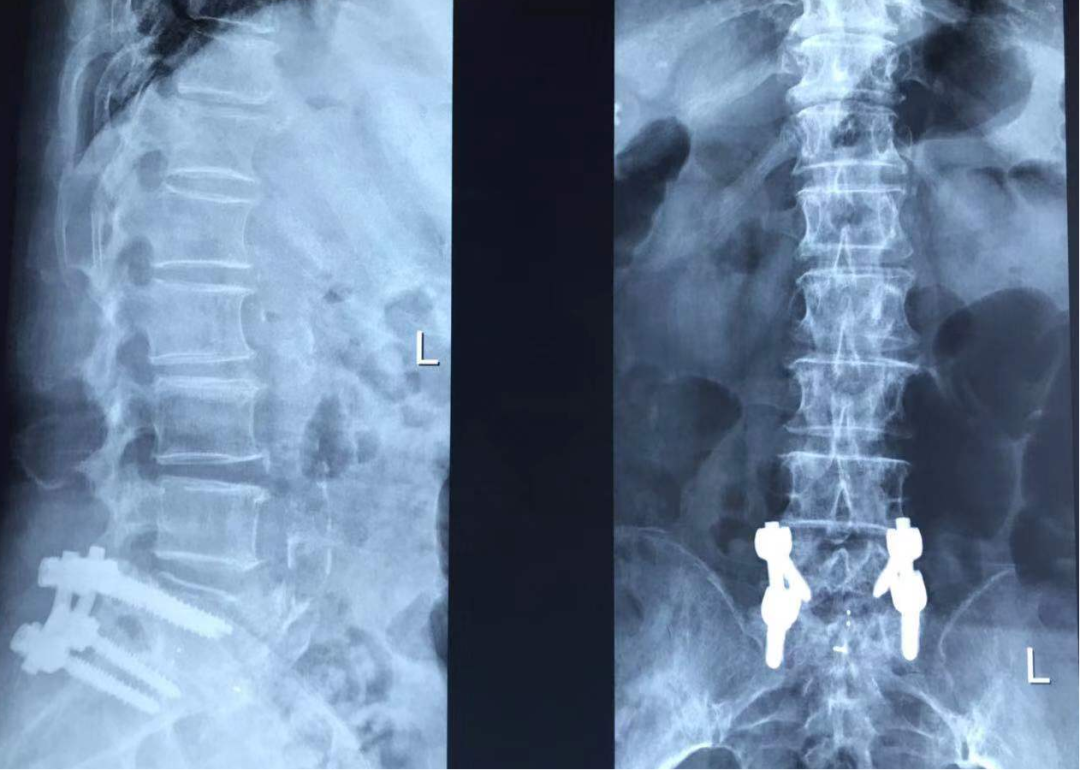

♦ 影像学检查:

腰椎平片示:腰椎术后改变。